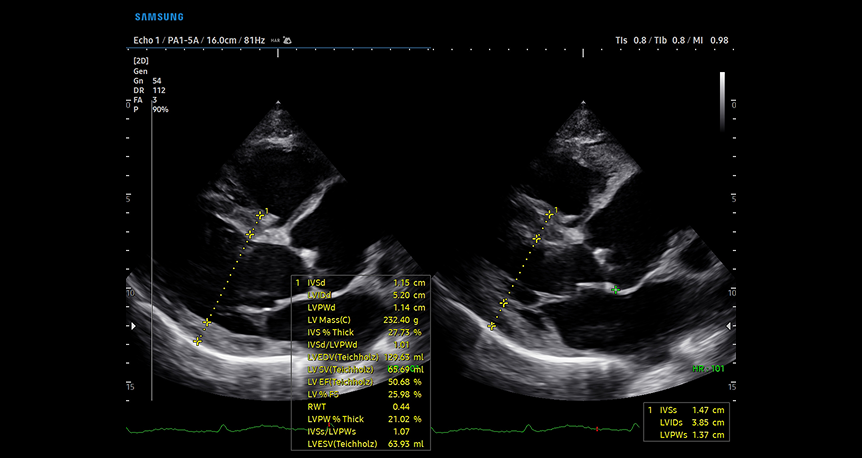

HeartAssist™ 1

HeartAssist AI-powered cardiac measurement tool providing automatic classification of ultrasound images with precise dimensional analysis and side-by-side comparison views

HeartAssist™, una funzione basata sulla tecnologia Deep Learning, fornisce una classificazione automatica dell'immagine ecografica nelle visualizzazioni di misurazione necessarie per la diagnosi cardiaca e fornisce i risultati della misurazione.